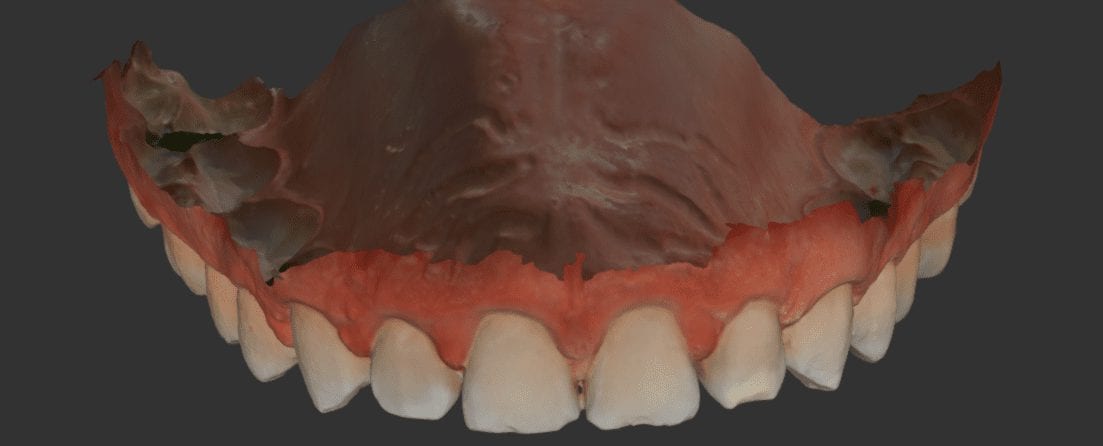

One of the greatest advantages of digital impressions is the ability to copy a pre-existing condition. This has a lot of benefits, one of which is that the patient will […]

There are many clinical advantages to taking digital impressions over traditional ones. Some of these concepts you may not appreciate until you are a user. We break these down into […]